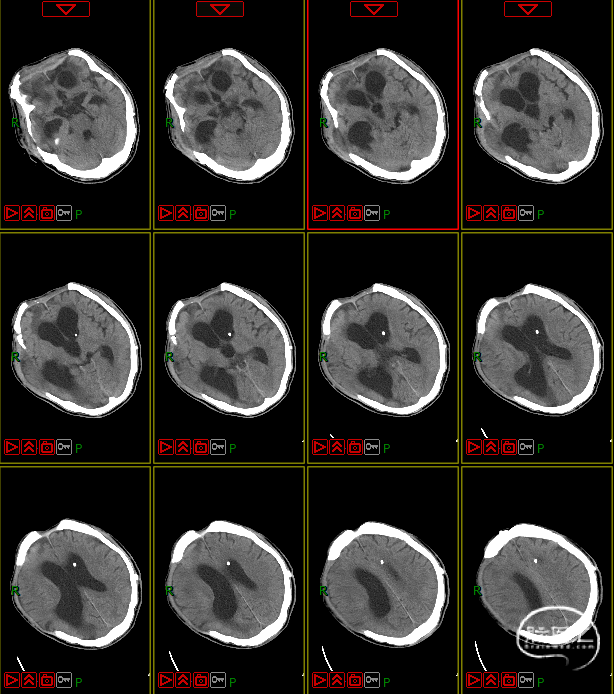

第五阶段(颅骨修补术)

7月16日行PEEK材料颅骨缺损修补术。

颅骨修补后对颅内压的影响

颅骨修补对颅内压的直接作用:颅骨修补后可恢复颅内压力分布,使得脑组织各个部位受到的压力相对平衡。

颅骨修补对脑组织的影响:颅骨修补使得脑组织重新获得硬质的保护,不易受到外界冲击,同时脑组织的支撑力加强,不易导致脑移位。

颅骨修补对脑脊液循环的影响:颅骨修补可能恢复脑脊液的正常循环,重新恢复脑脊液正常的分泌与吸收。

颅骨修补对血管调节的影响:颅骨修补可在一定程度上恢复脑血管的调节功能,让脑血流量正常,进而恢复颅内压的稳定。